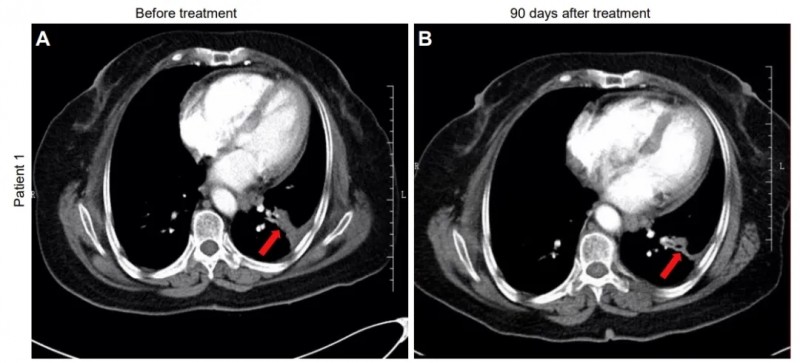

一项编号为NCT02843204的临床研究,评估了帕博利珠单抗(PD-1抑制剂)联合NK细胞治疗晚期NSCLC的安全性与有效性。研究纳入109例既往治疗失败、PD-L1表达阳性(TPS≥1%)的患者,分为联合治疗组和单药组。

结果突出:

- 客观缓解率(ORR)提升明显:联合组ORR为36.4%,显著高于单药组的18.5%;

- 中位总生存期(OS)延长2.2个月(15.5个月 vs 13.3个月),且多疗程NK输注患者OS达18.5个月;

- 中位无进展生存(PFS)达6.5个月,优于对照组的4.3个月。

典型病例中,一位68岁女性患者治疗90天后,肺内肿瘤明显缩小;另一例57岁男性患者同样达到部分缓解(PR),肿块显著缩小。

图片来源:JCI,版权归原作者所有

这一方案被誉为晚期肺癌的“黄金组合”,不仅提高客观缓解率,还显著延长患者生存,是免疫联合治疗的重要方向。